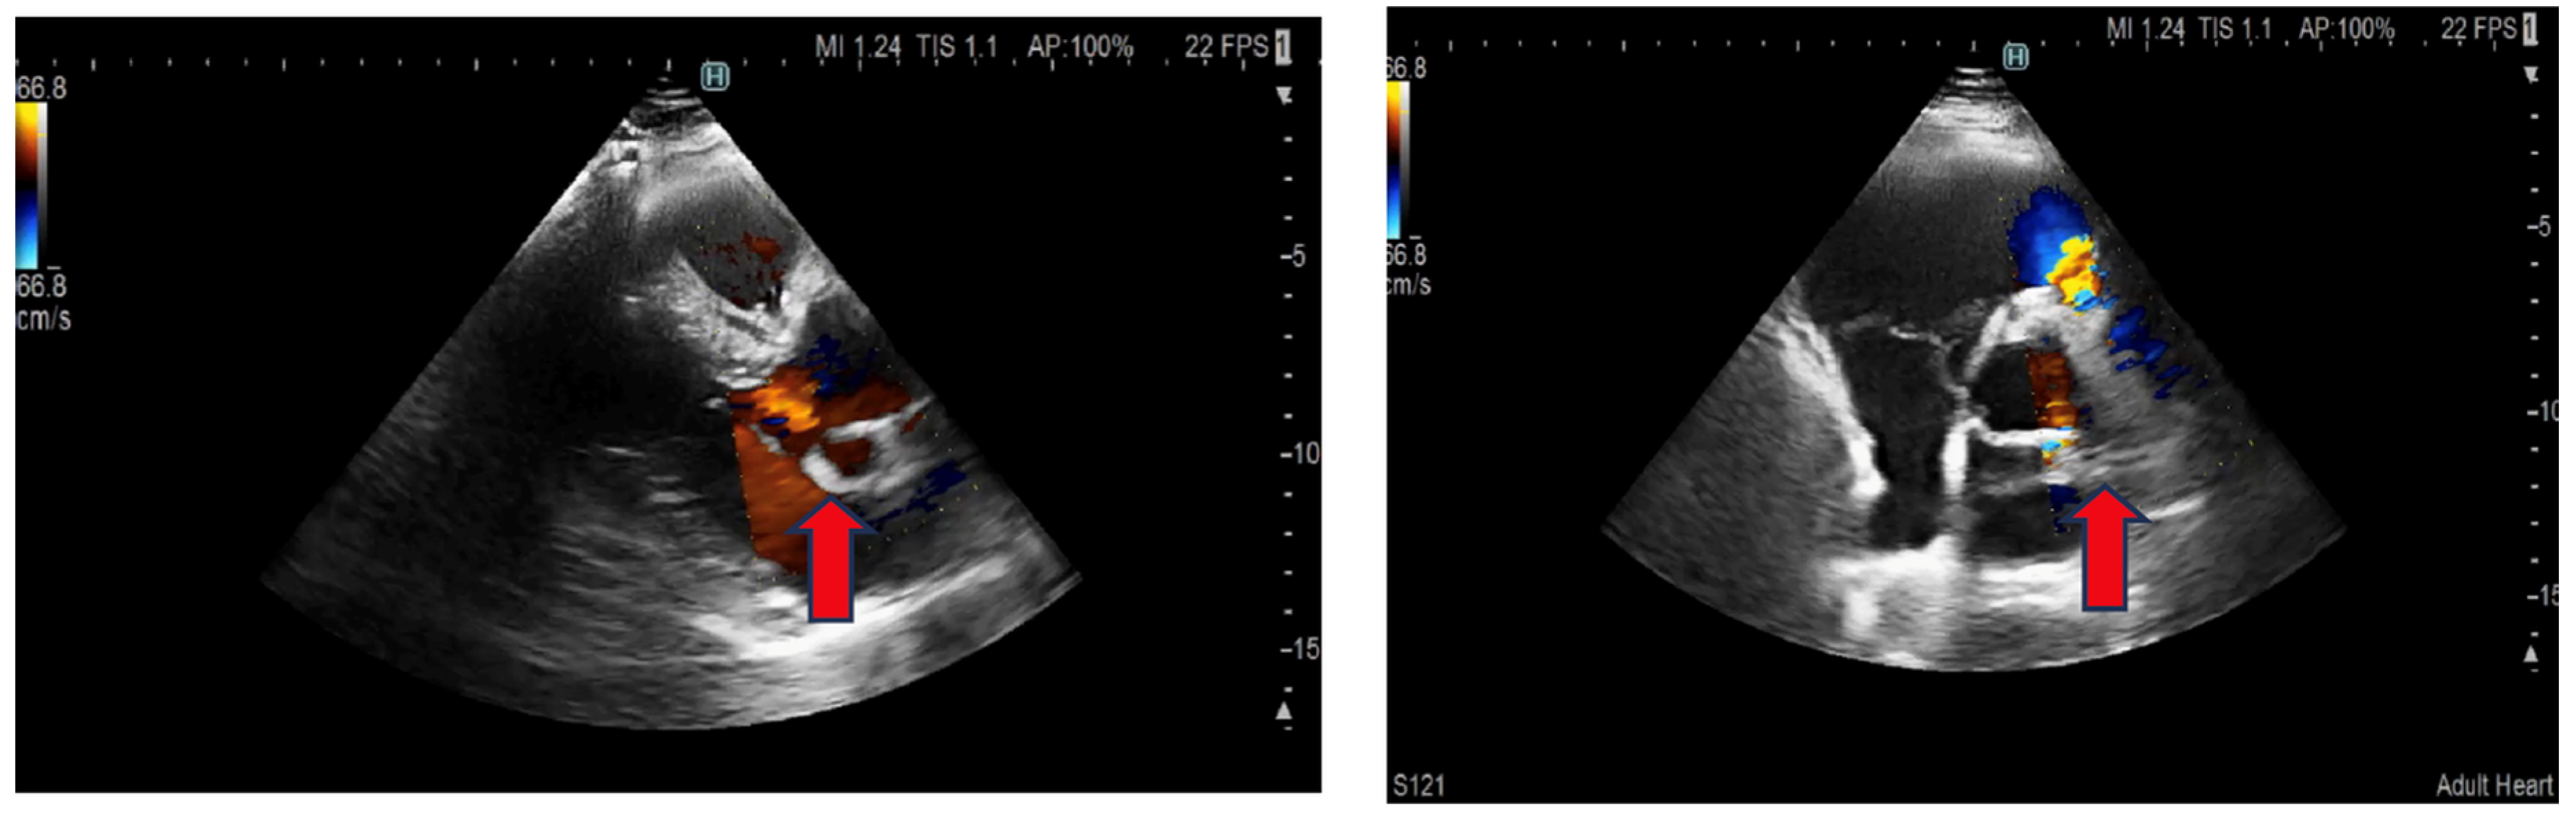

2. Case Presentation